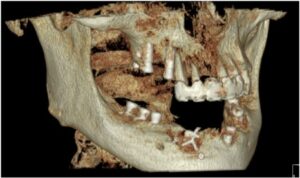

정밀한 검사를 위해

파노라마 사진을 촬영해 보았더니

아래턱 치아들이

심각한 골흡수를 보이고 있는

만성 치주염 상태로

전체 발치가 불가피한 상황이었습니다.

양산수면치과 에이디중부치과에서는

임플란트 식립을 진행하기 전

파노라마 사진과 3D CT 사진 촬영을 통해

위턱의 경우 상악동과의 거리,

아래턱 하방으로 지나가는

하치조 신경관의 위치,

잔존 치조골의 양과 두께,

눈에 보이지 않는 해부학적 구조물 등을

면밀하게 확인하는 과정을 거쳤으며,

이러한 결과를 토대로

임플란트를 식립하기 좋은 위치를 선정하고

식립 될 Fixture의 굵기와 길이,

식립 방향 등을

컴퓨터 분석과 시뮬레이션을 통해

미리 파악하는 과정을 거쳤는데요.